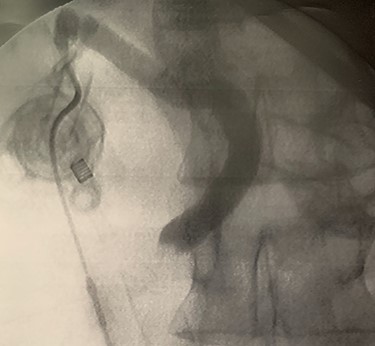

A trans-cystic cholangiography was then performed, using a 5.0 Fr COOK® Medical ureteral catheter inserted through epigastrium. The augmented caliber of CBD and the presence of prepapillary lithiasis were confirmed. No contrast could pass into the duodenum (Fig. 3).

Trans-cystic cholangiography demonstrating prepapillary lithiasis.